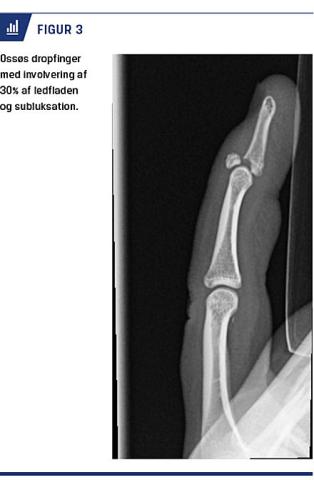

Frakturluksationer er hyppigst dorsale [22] og ses bedst i lateral projektion. Subluksationer ses som et

V-formet hul i den dorsale ledlinje (V-tegn) [23]. Der forekommer ofte læsion eller avulsionsfraktur af volarpladen med tab af volar støtte [2]. Mindre skader behandles med buddy taping og tidlig intensiv træning for at forhindre senfølger. Ved større avulsionsfragmenter kan de kollaterale ligamenter miste kontakten til mellemphalanx, som derfor sublukserer dorsalt (Figur 2) [24]. Volare frakturluksationer kan være ledsaget af

læsion af ekstensorsenens centralsnip, og der kan ses hyperfleksion med manglende ekstension i PIP-leddet (Elsons test) [2], hvilket kan være svært at teste akut. Frakturluksationer betragtes som stabile, når mindre end 30% af ledfladen er involveret, og når en eventuel subluksation forbliver reponeret i mindre end 30 graders fleksion [23]. Derudover skal leddet kunne ekstenderes og flekteres i en glidende bevægelse [3]. Frakturluksationer behandles med extension block-skinne i fuld fleksion, men med begrænset ekstension i PIP-leddet [22]. Over tre uger øges ekstensionen gradvist [23]. Volare frakturluksationer behandles med skinne i fuld ekstension og begrænset fleksion [2]. Ved involvering af mere end halvdelen af ledfladen er frakturluksationer ustabile [3]. Der kan foretages extension block pinning, hvor der sættes en K-tråd intraartikulært i den proksimale phalanx for at blokere ekstensionen i PIP-leddet og dermed forhindre subluksation eller luksation [23]. Ved kominutte frakturer af basis af mellemphalanx kan man anvende ekstern fiksering [22], eventuelt kombineret med intern fiksering og tidlig aktiv bevægelse [23]. Teknikken kan være udfordrende, og der er risiko for infektion og frakturskred [23].